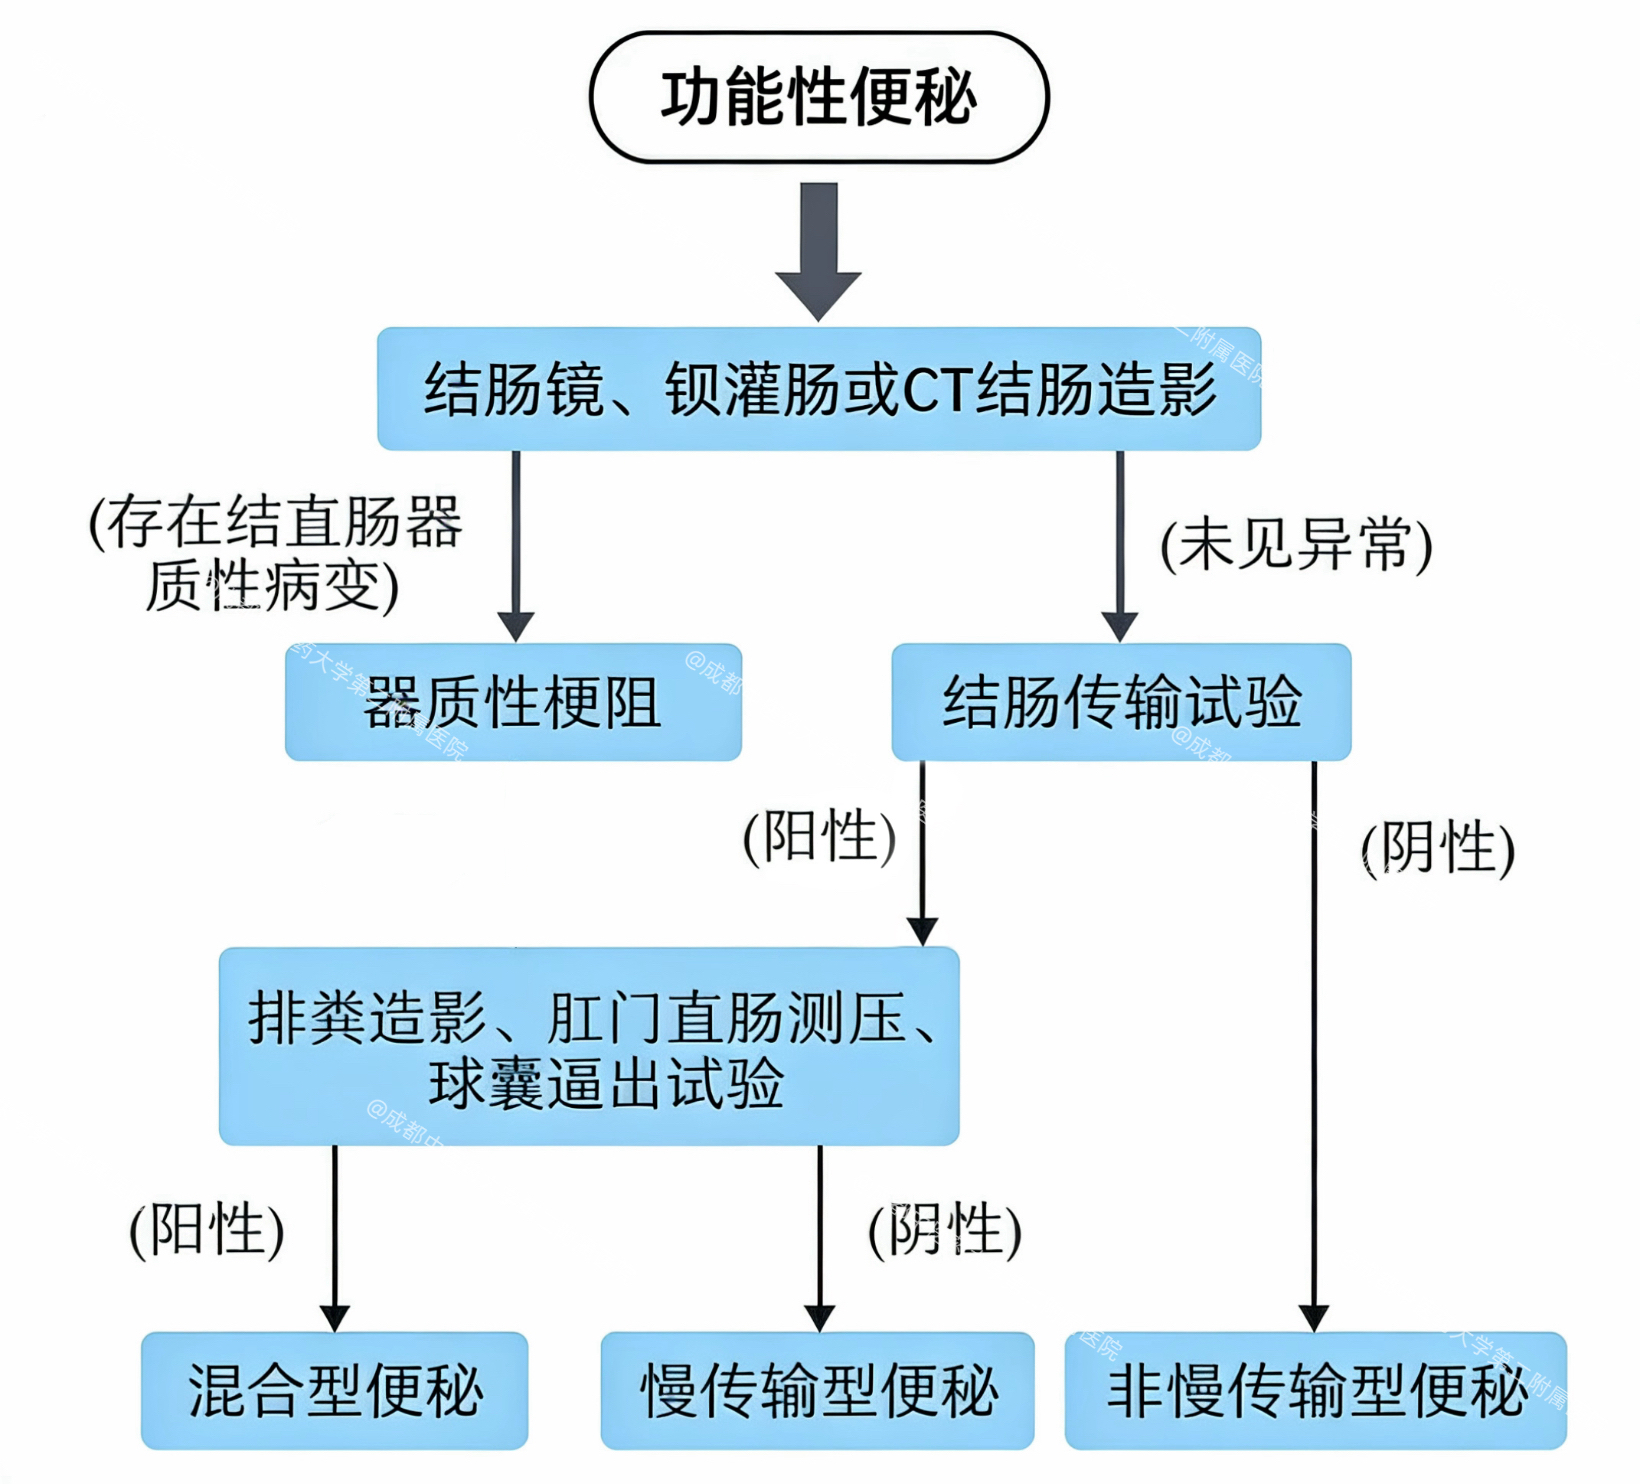

慢性便秘中,慢传输型便秘(STC)尤为常见,表现为排便次数减少(每周少于3次)、粪便干结、腹胀、病程6个月以上等。结肠传输试验能科学评估肠道蠕动效率,就像给肠道装个“GPS”,精准追踪食物残渣的旅行进度,是诊断STC的有效手段!

3.需明确便秘类型者:慢传输型vs.出口梗阻型

四、结果分析:肠道“慢不慢”一看便知!

1.正常:48小时残留率≤20%,肠道传输效率满分!

2.慢传输型便秘:48小时残留率>20%,标记物均匀分布于结肠

3.出口梗阻型便秘:48小时残留率>20%,标记物集中于直肠

4.混合型便秘:残留标记物分散在结肠且有集中于直肠或乙状结肠,需进一步检查